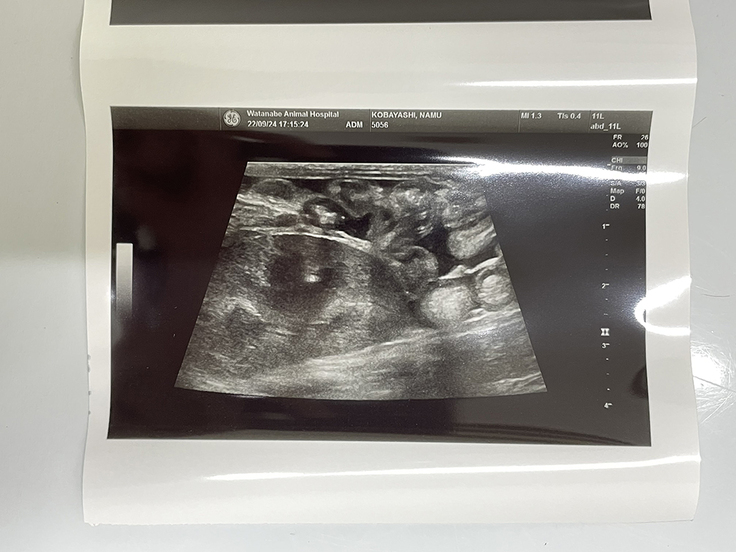

9月24日現在↑ 事故の影響で腹腔内に溜まっている腹水(黒い部分)のエコー

排尿の回数は少し多いが、排便は順調。